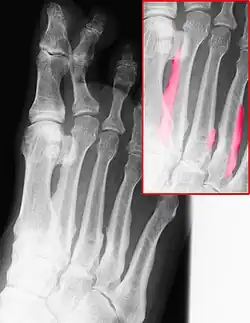

Die Melorheostose (griechisch: μέλι = Honig, ῥεῦμα = Fließen, ὀστέον = Knochen) ist eine seltene abschnittsweise Verdickung des Knochens, meist an den Extremitäten. Der Knochenstoffwechsel ist ungestört.

Nach dem Erstbeschreiber wird die Melorheostose auch Léri-Syndrom (André Léri, Neurologe, Paris, 1875–1930) genannt. Wegen des röntgenologischen Erscheinungsbildes sind auch die Bezeichnungen Kerzenwachskrankheit, Wachsknochenerkrankung gebräuchlich. Englisch: Léri's melorheostosis, Léri-Joanny syndrome, candle bone disease.

Die Diagnose wird im Röntgenbild gestellt. Es finden sich auf Dermatome begrenzte streifenartige sklerosierte Verdichtungen an Wachstropfen erinnernd, die von einer Kerze abfließen.